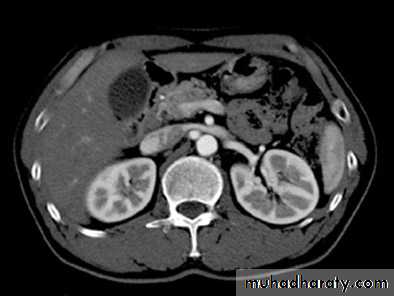

Cortico-medullary phase: After 35-40 seconds:

The only parts of the renal tract which have enhanced are the renal arteries and the cortex.Useful for evaluation of the renal arteries (which may be reformatted as CT angiogram) and for evaluation of highly vascular renal tumors.

Native CT…For evaluation of any renal stones or abnormal calcification.

CT scanContrast enhanced CT scan through the kidneys in nephrogram phase 90-100 seconds following contrast administration and would show renal lesions well.

Contrast enhanced CT scan through the kidneys in pyelogram phase (showing excretion of contrast into the collecting system). This is approximately 10-15 minutes following contrast administration and would show urothelial lesions well, such as transitional cell carcinoma, stones, blood clots.